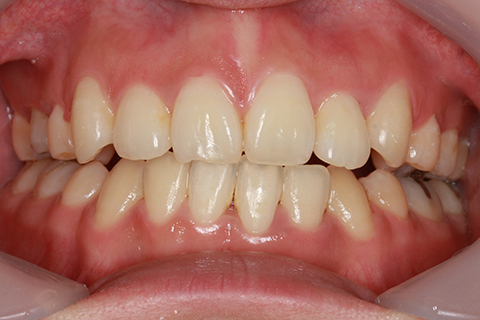

ハーフリンガル矯正3:上の歯のみ舌側矯正で治療(矯正期間24ヶ月)

治療前

治療後

- 年齢・性別

- 25歳女性

- 治療期間

- 2年0ヶ月

- 抜歯

- 上下4番抜歯

- 治療費

- 110万円

- 治療内容

- 施術の副作用(リスク)

- 表側矯正と比較して、力学的な操作性が複雑なため、ボーイングエフェクトを起こしやすい。